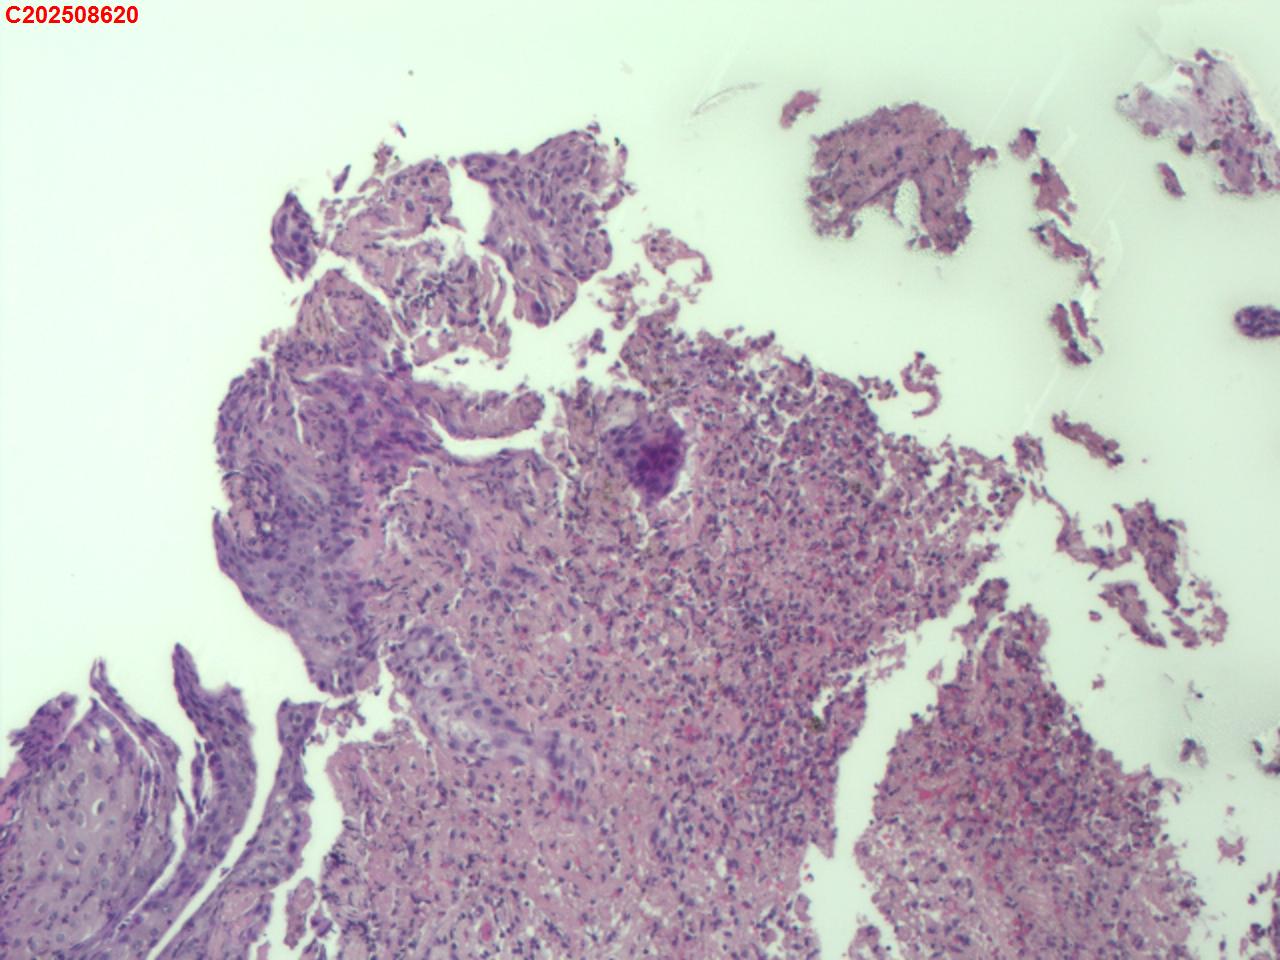

CT示:考虑右肺上叶炎症伴肺实变,右肺上叶前段支气管显示不明确,建议治疗后复查或支气管镜检查。纵膈多发淋巴结增大。右侧胸腔积液。主动脉及冠状动脉钙化。食道裂孔疝。

气管镜检查示:右肺上叶前段支气管开口可见脓苔附着,支气管开口狭窄,内可见灰黑色新生物阻塞右肺上叶前段支气管管腔。

者缘于10余天前无明显诱因出现发热,体温最高39.5℃,咳嗽、咳少量白痰,活动后气短,无盗汗,无咯血,无胸痛,无鼻塞、流涕,无恶心、呕吐,无腹痛、腹泻。就诊廊坊市第四人民医院,查胸部CT示:考虑右肺上叶炎症伴肺实变,右肺上叶前段支气管显示不明确,建议治疗后复查或支气管镜检查。纵膈多发淋巴结增大。右侧胸腔积液。主动脉及冠状动脉钙化。食道裂孔疝。结核感染T细胞检测阳性。气管镜检查示:左侧主支气管、上叶、下叶及各段支气管未见异常。右侧主支气管未见异常。右侧中间段支气管可见碳沫沉积。右肺上叶前段支气管开口可见脓苔附着,支气管开口狭窄,内可见灰黑色新生物阻塞右肺上叶前段支气管管腔。肺泡灌洗液查结核分枝杆菌复合群阳性。

有坏死,有上皮样细胞,做个抗酸染色看看。